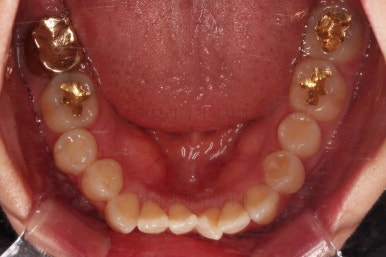

1. 초진

부산개방교합 키다리아저씨치과에 처음 내원 시 입안의 모습입니다.

전반적으로 치열이 삐뚤고요.

앞니쪽이 다물어지지 않는 개방교합(오픈바이트, open bite) 을 보였습니다.

어금니 맞물림을 보면 앵글씨 2급 부정교합 양상이어서 위아랫니가 모두 1대1로 부딪히고 있는 상태였습니다.